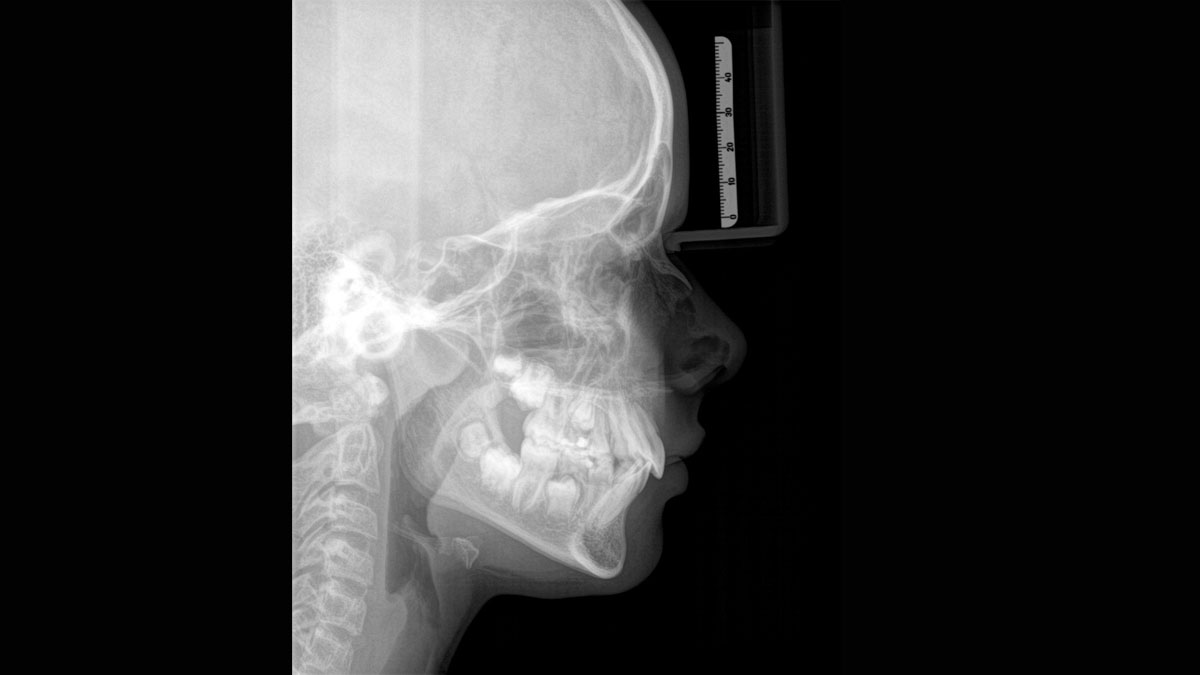

Para obtener imágenes panorámicas excepcionales con alta nitidez. Puede elegir un brazo cefalométrico derecho o izquierdo opcional, que puede reacondicionarse en cualquier momento

Gracias al modo de dosis baja optimizado con un filtro exclusivo, es posible obtener radiografías de estructuras densas, como huesos, a una dosis enormemente reducida. Esto hace que la dosis baja inteligente sea una opción atractiva y eficiente para muchas situaciones clínicas. Ya sea en ortodoncia o implantología, con el equipamiento Dentsply Sirona encontrará la configuración óptima para cada caso.